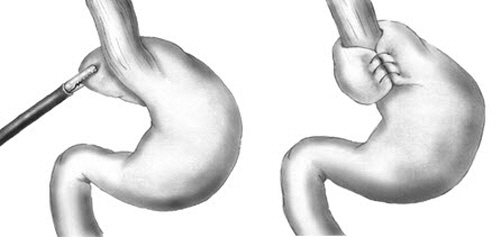

식도와 위 사이에 있는 하부 식도 괄약근과 흉부와 복부를 구분하는 횡격막이 위에서 식도로 역류되는 것을 막아주는 역할을 하는데, 하부 식도 괄약근의 조이는 힘이 약해지거나 식도가 통과되어 내려오는 횡격막의 틈이 벌어져 열공탈장이 된 경우 위식도역류질환 또는 역류성 식도염이 발생되며, 항역류 수술(복강경 위저추벽성형술)은 이렇게 느슨해진 식도 하부를 복강경을 이용해 감싸주고 횡격막의 틈을 막아주는 수술로, 재발이 잘되는 환자들에게 보다 확실한 치료법이 될 수 있다.

이 같은 치료법은 우리나라보다 위식도 역류질환 유병율이 두 배 이상 높은 미국이나 유럽에서는 이미 50년 전부터 시행되어 효과와 안전성이 증명된 수술법이지만, 국내에서는 과거 개복 수술에 대한 부담과 인식 미비로 그동안 매우 드물게 시행됐으며 그동안 복강경 수술이 발전하면서 항역류 수술도 급속히 발전해 위식도 역류성질환의 치료의 한 방법이 됐지만 아직도 극소수의 환자만이 수술적 방법을 선택하고 있다.